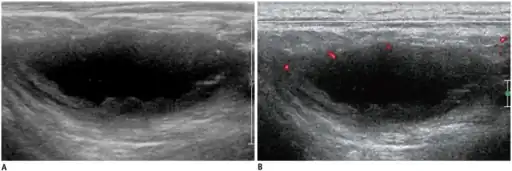

a,b)Individual diagnosed with tuberculous lymphadenitis -ultrasonography/Doppler ultrasonography